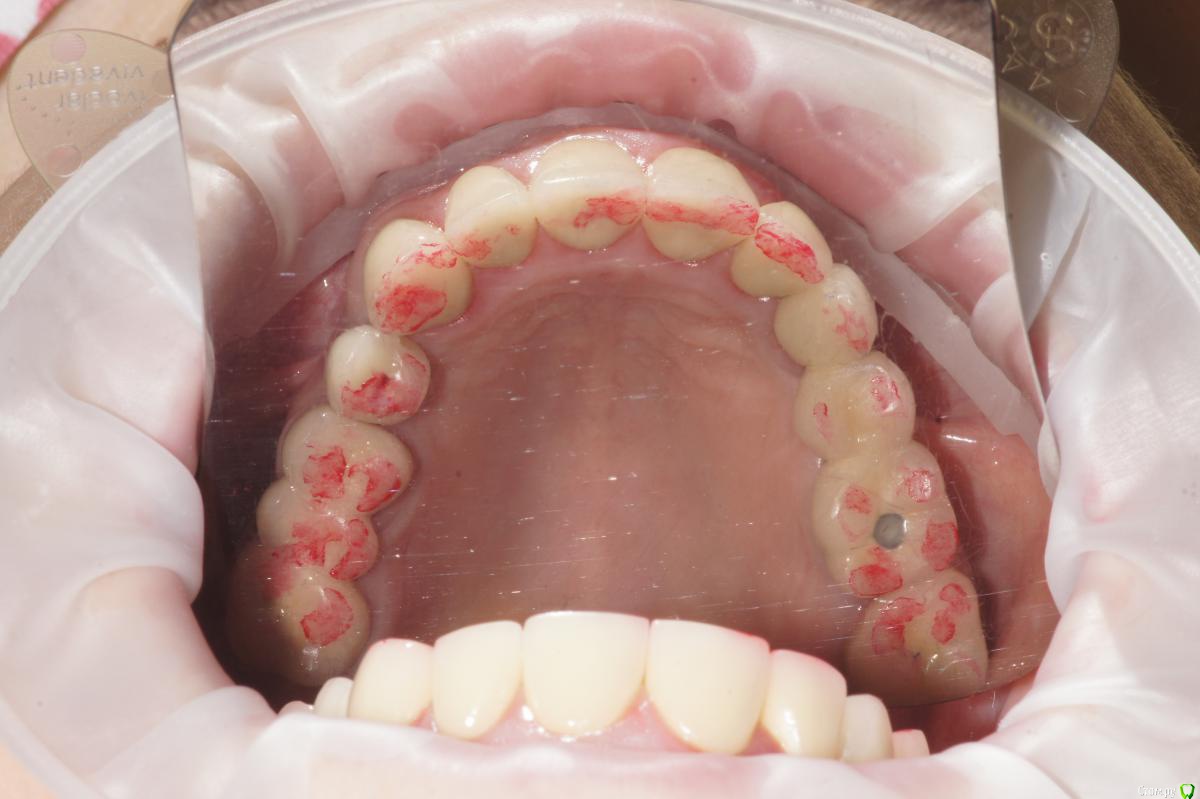

Alexandr_doc Опубликовано 21 сентября, 2018 Поделиться Опубликовано 21 сентября, 2018 Доброго всем времени! Пациентку протезировал доктор, которого уволили по ряду причин, обратилась ко мне на этапе после протезирования с жалобами на болезненность в области фронтальной группы зубов 1.2, 1.1, 2.1, 2.2, 2.3 при дотрагивании языком или пальцем. Перкуссия положительная как в вертикальном так и горизонтальном направлении. Установлены одиночные керамические коронки на каркасе из диоксида циркона. Отек, покраснение в области переходной складки отсутствует, также отсутствует болезненность при пальпации. Подвижность 1 степени. Прилагаю фотографии на этапе обращения. Ранее, на этапе протезирования было принято решение о депульпировании фронтальной группы тк присутствовала пульпитная симптоматика, после чего состояние улучшилось и остается стабильным по сей день. Предположил несколько причин оставшейся симптоматики: 1) несостоятельно проведенное эндо лечение - вариант отмел тк по прицельным снимкам и кт отсутсвуют очаги воспалительных процессов 2) некорректно изготовленные искуственные коронки ( глубокая поддесневая препаровка и агрессивный контур коронки ) 3) - окклюзионная перегрузка. Совместно с пацинеткой принято решение о снятии коронок во фронтальном отделе, была предупреждена о том, что возможно не получить хорошей динамики. С переменным успехом картина после нескольких корректировок временных коронок остается преждней. Болезненность на прежднем уровне, плюс по ходу наблюдения пришлось снять мост с опорой на уровне имплантатов, тк имели место быть воспалительные процессы в проекции имплантата 1.5. С удовольствием отвечу на все вопросы и приму любую критику. Ссылка на комментарий

Alexandr_doc Опубликовано 21 сентября, 2018 Автор Поделиться Опубликовано 21 сентября, 2018 Маргинальной гингивит. Нависающие края? Мягкий налет под коронками? Остатки цемента? Скоро будет пародонтит.Специально приложил прицельные снимки с временными коронками, где нависающие края? Цемента, лежащего тоннами там нет, думаю, что с корявыми временными коронками выкладывать пост не стал бы Ссылка на комментарий